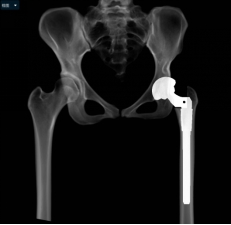

通过术前充分的准备,小张的手术也如约而至。当天在术中,毕郑刚和耿硕发现小张的患侧股骨头和髋臼都存在发育异常,没有软骨而且形状较不规则,难以契合,保髋方案不可取,于是只能采取方案二:全髋关节置换术。因为术前提前进行了规划,相应型号的假体也已经提前准备,髋臼假体及股骨假体安装得较为顺利。然而和预料的一样,在髋关节假体尝试复位时软组织张力较大,很难进行复位。因为在术前患侧股骨通过极限力量牵引验证了不截骨复位的可能性是存在的,为了能够让患者一期恢复腿长,避免二次手术,毕郑刚和耿硕决定通过进行软组织的松解来复位,选择了不进行股骨截骨,但是考验手术技术。经过对髋关节周围软组织的松解后,最终假体复位成功,随后通过比对双下肢长度,提示等长,关节活动度良好,宣告手术一期顺利完成。术后小张返回病房,因为未进行截骨仍有软组织张力大致神经血管等损伤的风险,术后嘱其行患肢适度屈髋屈膝位来减缓软组织张力,2~3周内逐渐伸直。术后通过查体,小张并未出现神经的损伤症状,手术成功。

(术后X线)